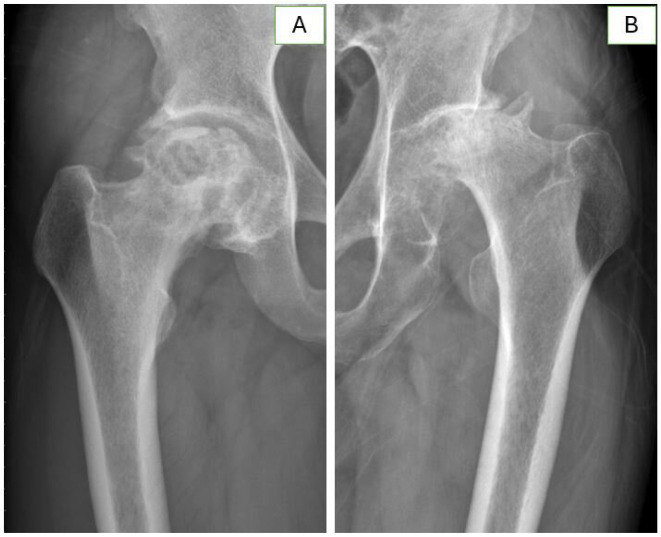

Purpose: Total hip arthroplasty (THA) is the only definitive treatment for rapidly destructive coxarthrosis (RDC). THA for RDC has significantly higher perioperative blood loss with a greater requirement for transfusion than non-RDC primary THAs. Given the rarity of the disease, this study aimed to investigate perioperative and long-term outcomes of cementless THA for RDC that developed from osteonecrosis of the femoral head (ONFH).

Materials and methods: Each of 26 RDC patients was matched to a patient with typical advanced-stage ONFH for comparison, according to age, sex, American Society of Anesthesiologists classification, and the type of implant used. As a primary outcome, perioperative blood loss was calculated as the sum of compensated and uncompensated blood loss.

Results: The RDC group had a significantly larger amount of total perioperative blood loss in comparison to the group with typical ONFH (791.5 mL vs. 511.2 mL, P=0.034), which was primarily attributable to compensated blood loss (496.1 mL vs. 141.5 mL, P=0.024), as uncompensated blood loss was not significantly different (P=0.152). Intraoperative transfusion volume was significantly higher in the RDC group (234.6 mL vs. 46.2 mL, P=0.007), while the difference in postoperative transfusion was marginally significant (P=0.092).

Conclusion: THA for RDC was accompanied by a higher perioperative blood loss, attributable mainly to a significant difference in the amount of intraoperative transfusion, in a matched comparison with patients with typical advanced-stage ONFH. However, extended operation time and prolonged hospitalization along with a large volume of transfusion did not translate into inferior long-term outcomes.